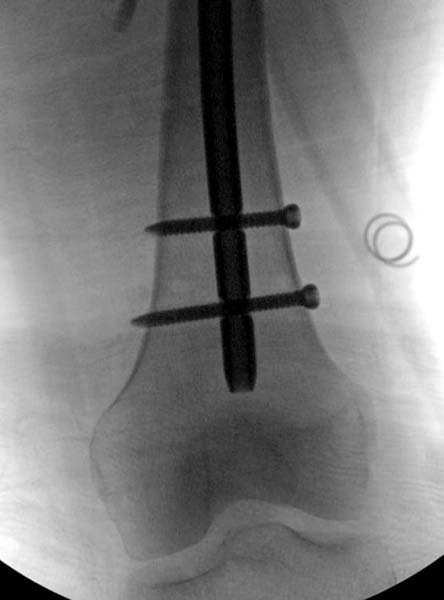

> стабильная.. На третьий день провели стабилизацию перелома бедра

> антеградным остеосинтезом.

> Для решения проблемы дистальной блокировки компания DigiMed недавно

> предложила систему блокировки без рентгена. Пока в стране только два набора

> и только для антеградных гвоздей, но компания работает над созданием

> устроиства для других гвоздей тоже..

> Результат первых случаев показала отсутствие разницы между занятиями на

> муляжах, а также Workshop и с удивительной точностью вывел латерально над

> кожей специальное сверло. Дальше по сверлу тонкий направитель и проводится

> сверление каннюлированным сверлом....